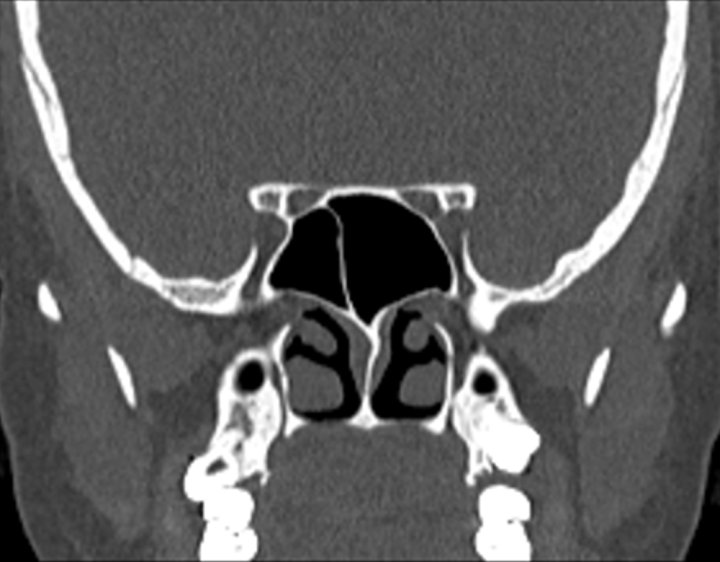

Click any image for labels.